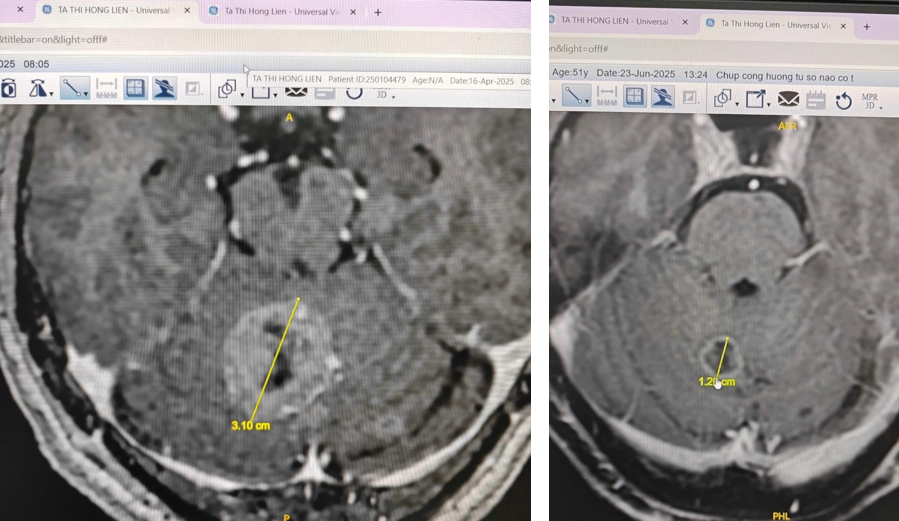

Professor Chan and his team assessed Lien’s condition, identifying a 3.1 cm brain tumor and a 25 mm x 35 mm lung tumor. The comprehensive treatment plan included two infusions of Super Transfer Factors, two infusions of Thymus MO, and two infusions of GCMAF to boost her immune system. Lien also underwent seven days of Hyperthermia therapy, using filtered infrared-A radiation (WIRA) to raise her body temperature, stimulate her immune response, and enhance treatment effectiveness. This therapy also helped alleviate pain and aided detoxification.

Following the treatment, the brain tumor shrunk from 3.1 cm to 1.2 cm, and the lung tumor decreased to 17 mm x 23 mm.

Brain tumor scan results: reduced from 3.10 cm (before) to 1.20 cm (after treatment) at European Wellness, thanks to Professor Mike Chan's treatment plan. Photo: European Wellness